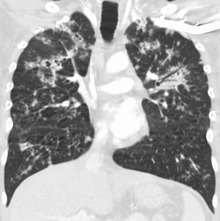

| Chest X ray showing miliary tuberculosis | |

Miliary tuberculosis is a form of tuberculosis that is characterized by a wide dissemination into the human body and by the tiny size of the lesions (1–5 mm). Its name comes from a distinctive pattern seen on a chest radiograph of many tiny spots distributed throughout the lung fields with the appearance similar to millet seeds—thus the term "miliary" tuberculosis. Miliary TB may infect any number of organs, including the lungs, liver, and spleen.[2] Miliary tuberculosis is present in about 2% of all reported cases of tuberculosis and accounts for up to 20% of all extra-pulmonary tuberculosis cases.[3]

Testing for miliary tuberculosis is conducted in a similar manner as for other forms of tuberculosis, although a number of tests must be conducted on a patient to confirm diagnosis.[5] Tests include chest x-ray, sputum culture, bronchoscopy, open lung biopsy, head CT/MRI, blood cultures, fundoscopy, and electrocardiography.[11] The tuberculosis (TB) blood test, also called an Interferon Gamma Release Assay or IGRA, is a way to diagnose latent TB. A variety of neurological complications have been noted in miliary tuberculosis patients—tuberculous meningitis and cerebral tuberculomas being the most frequent. However, a majority of patients improve following antituberculous treatment. Rarely lymphangitic spread of lung cancer could mimic miliary pattern of tuberculosis on regular chest X-ray. [16]